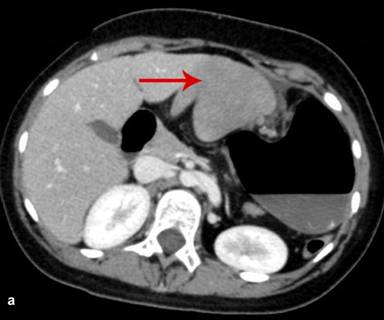

Figure 4. Axial CT scan abdomen shows an enlarged wandering spleen (red arrow), extending from the undersurface of the left lobe of the liver (a.) extending medially to the distended stomach up to the lower pole of the left kidney (b.). |

|